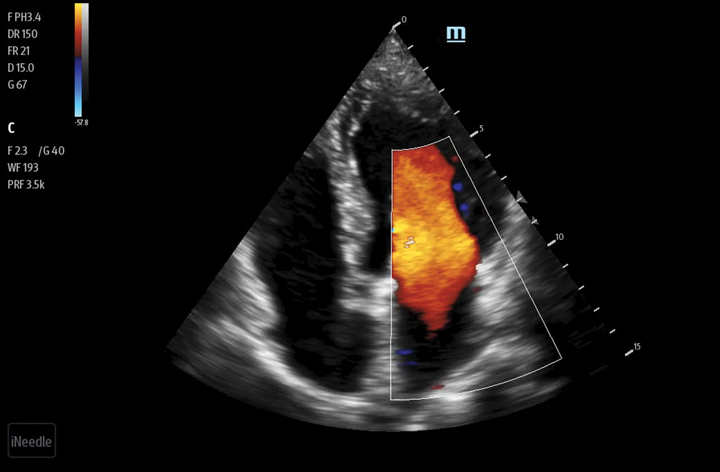

Needle Guidance